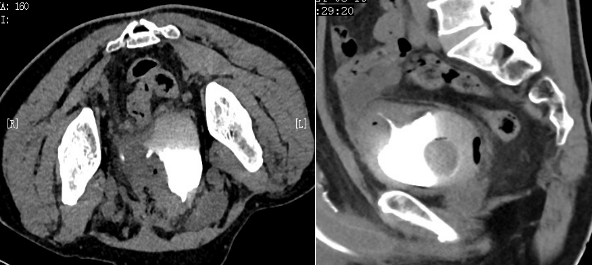

结肠癌患者侵犯膀胱左前上壁并瘘形成,CT俯卧位扫描,更好显示瘘道